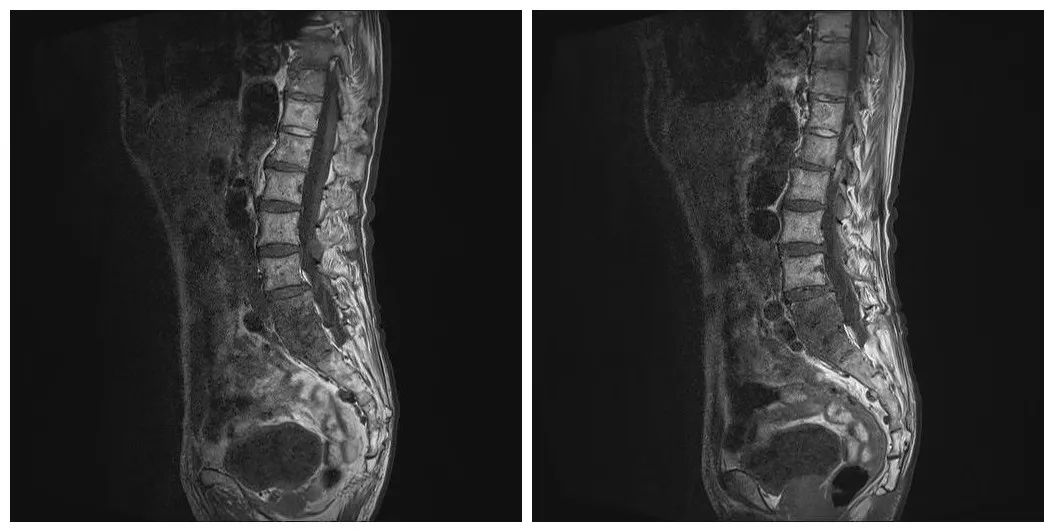

3月21日,复查腰椎MRI提示L5、S1椎体及周围软组织异常信号,考虑感染可能大,较前进展。T12椎体异常信号,血管瘤。腰椎退行性变并L4椎体不稳(图1)。

图1 患者腰椎MRI结果